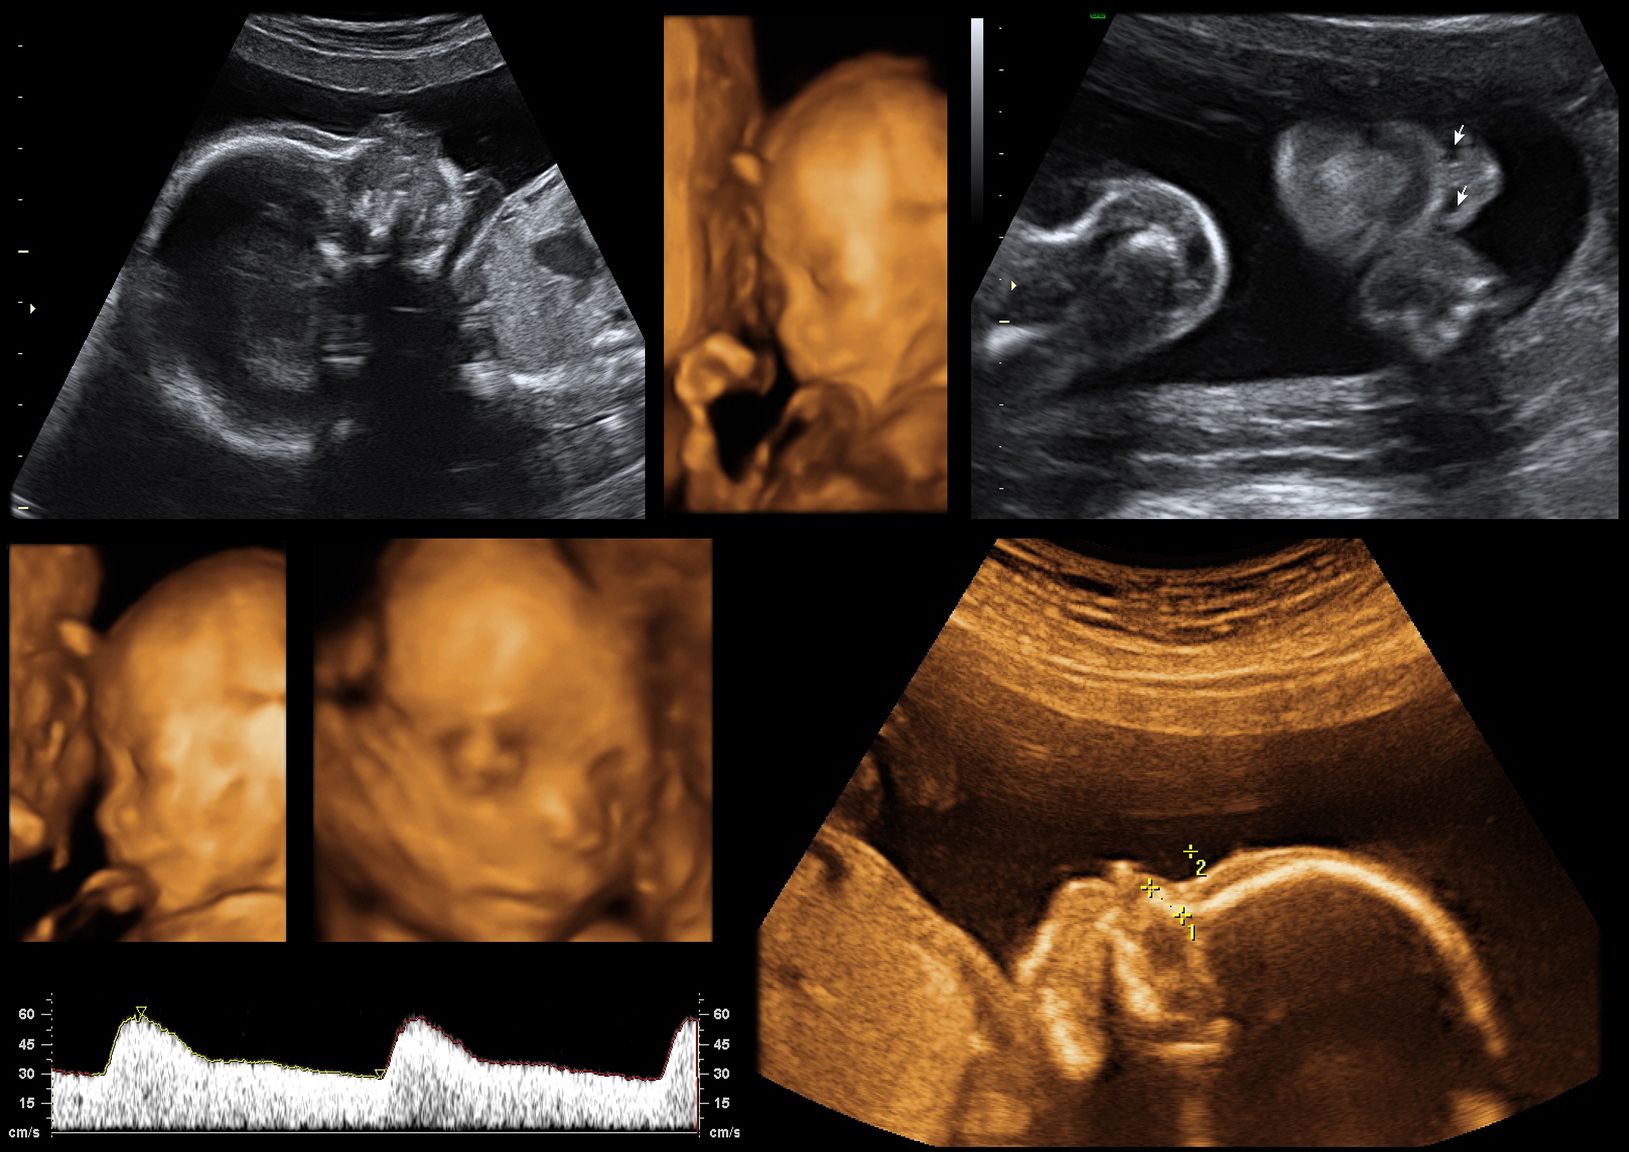

这个外星人是我的BB吗?本周拿到四维排畸彩超的结果单,医生会根据宝宝的头围、腹围、股骨长度等参数给你一个大致的结果:比如宝宝很健康,但是个子偏小,那么可能你得拼命多吃点有营养的东西,来满足宝宝的发育需要了。当然,假如出现唇线不连贯或者心脏有小孔等不幸的情况出现,医生可能会要求你下周再做一次进行确诊,之后你会面临艰难的抉择——是去是留。不过这个概率很小,况且这也体现了医疗科学的好处,减少出生缺陷对家庭而言意义重大,虽然此刻接受起来可能非常的艰难。